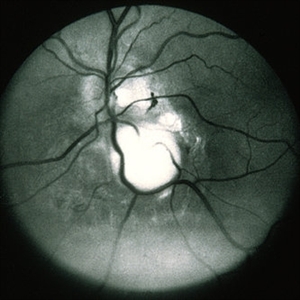

Toxocara Granuloma

Jun 4 2014 by Henry J. Kaplan, MD

Arteriovenous phase angiogram of the same patient shows staining of the granuloma and stippling hyperfluorescence around the lesion secondary to RPE window defect. #3

Condition/keywords: toxocara granuloma, toxocariasis